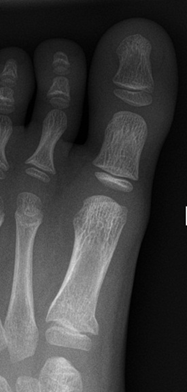

Toddler's fracture

- Follow up Orthopaedic Fracture Clinic in 1 week.